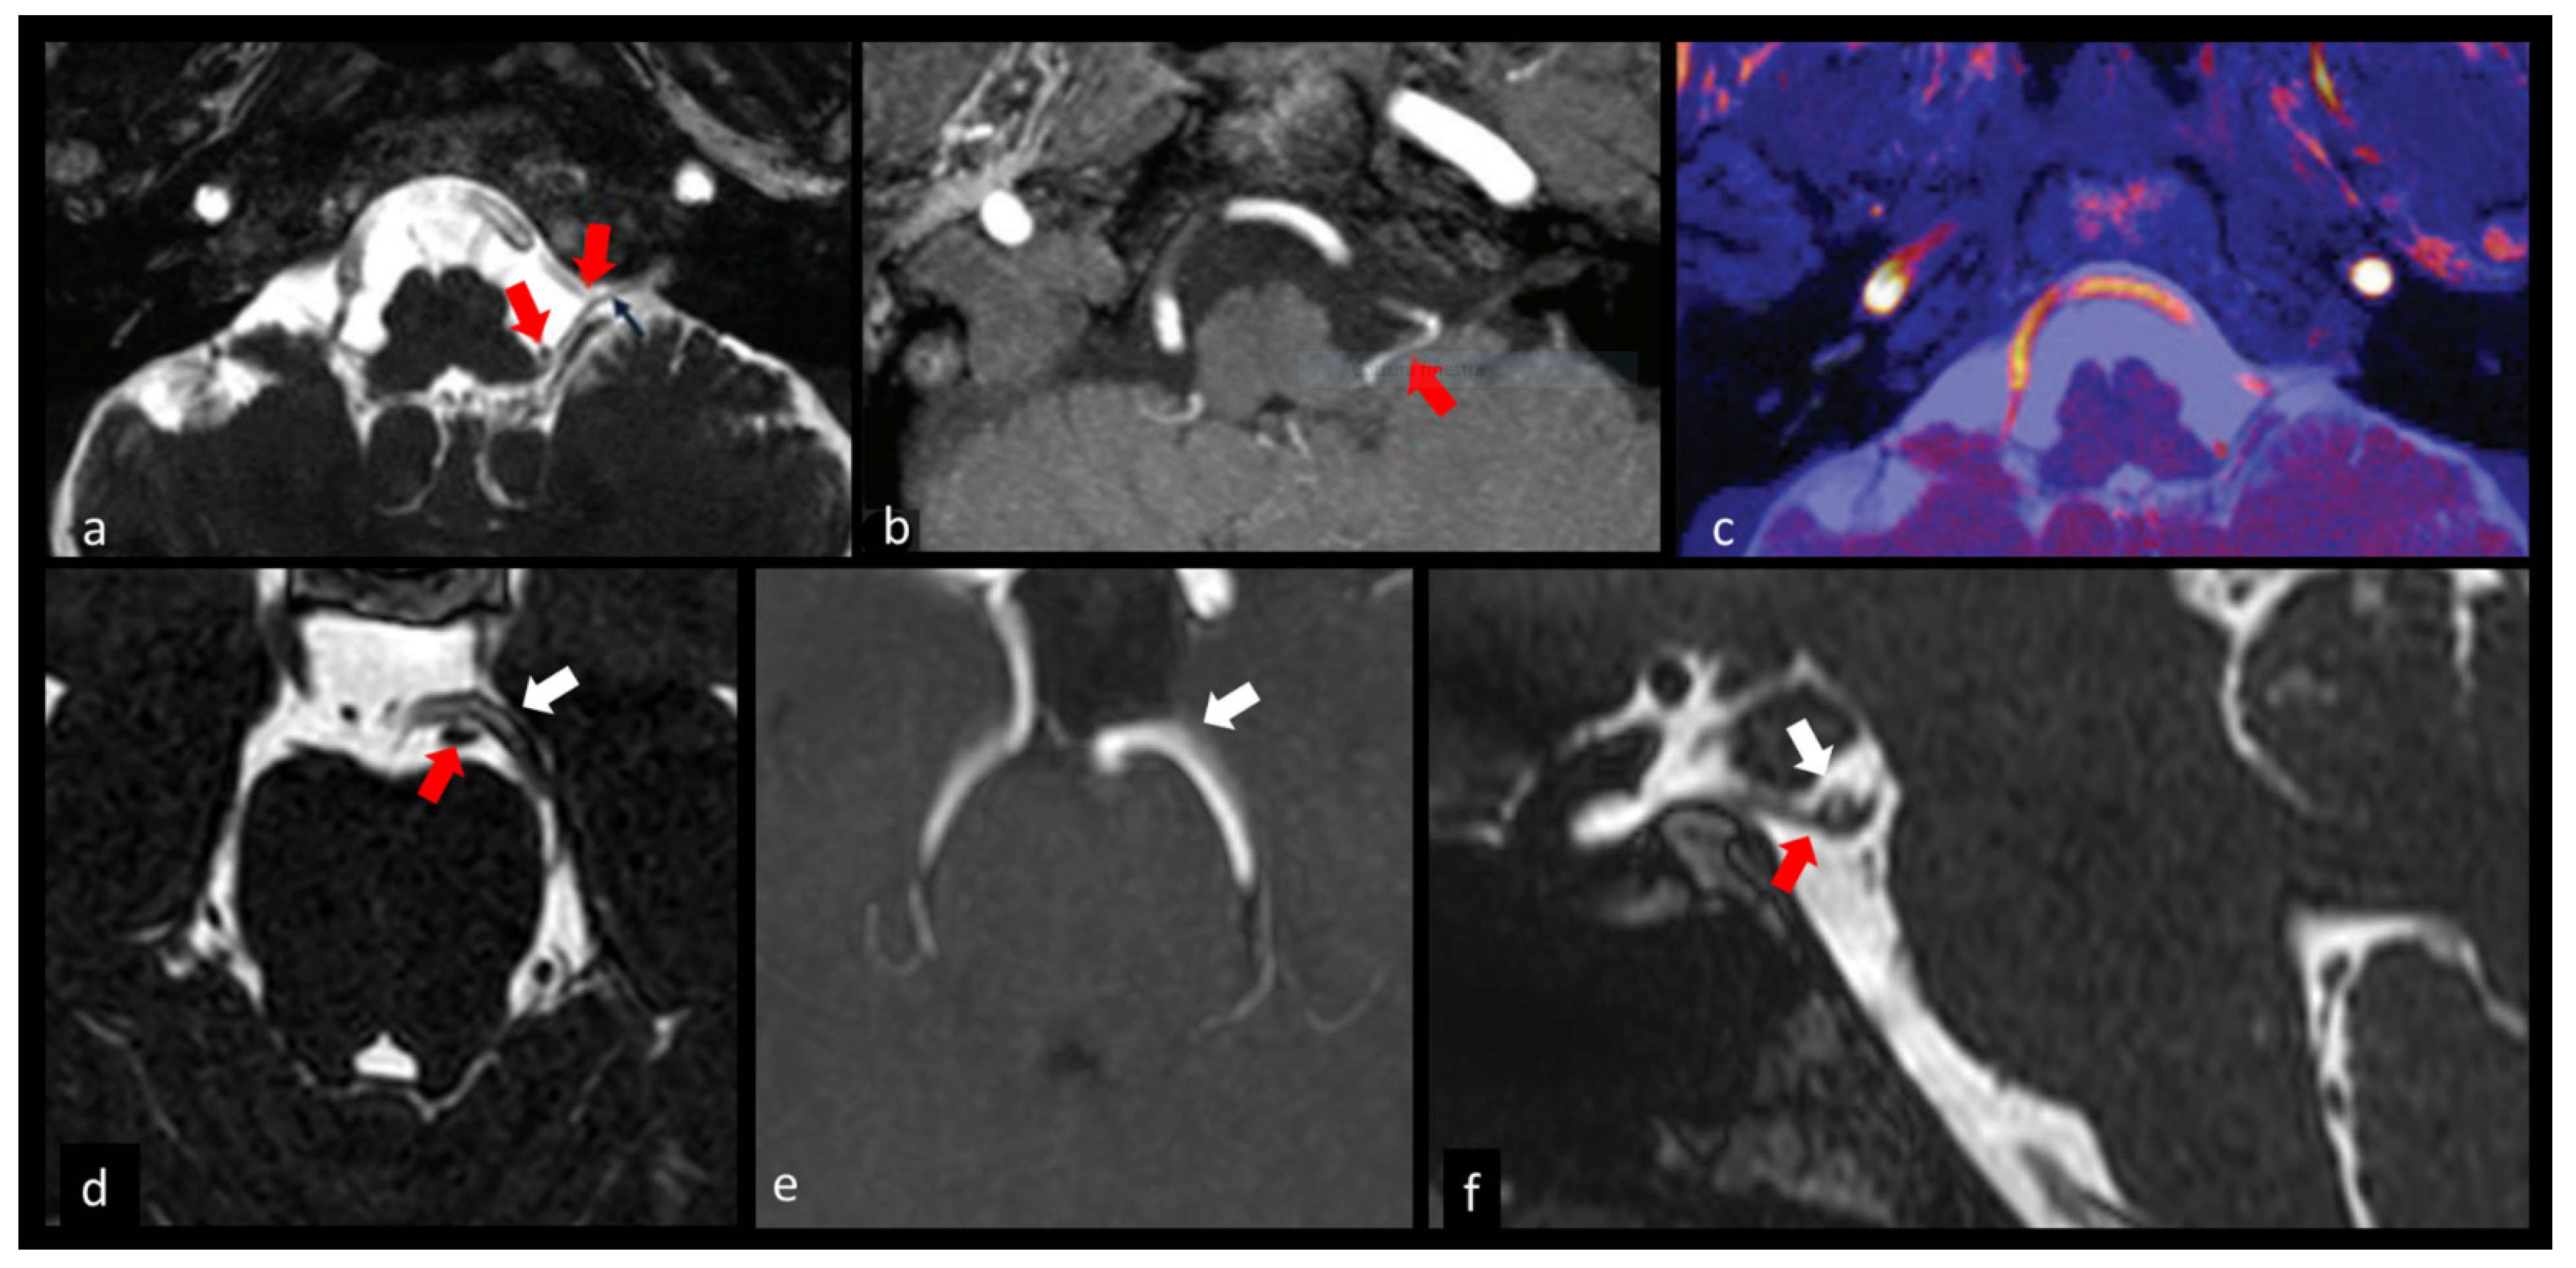

3.1.4. Trigeminal Nerve (V)

3.4. Cerebrovascular Pathology

- Granata, F.; Vinci, S.L.; Longo, M.; Bernava, G.; Caffo, M.; Cutugno, M.; Morabito, R.; Salamone, I.; Tomasello, F.; Alafaci, C. Advanced virtual magnetic resonance imaging (MRI) techniques in neurovascular conflict: Bidimensional image fusion and virtual cisternography. Radiol. Med. 2013, 118, 1045–1054. [Google Scholar] [CrossRef] [PubMed]

- Garcia, M.; Naraghi, R.; Zumbrunn, T.; Rösch, J.; Hastreiter, P.; Dörfler, A. High-resolution 3D-constructive interference in steady-state MR imaging and 3D time-of-flight MR angiography in neurovascular compression: A comparison between 3T and 1.5T. AJNR. Am. J. Neuroradiol. 2012, 33, 1251–1256. [Google Scholar] [CrossRef]